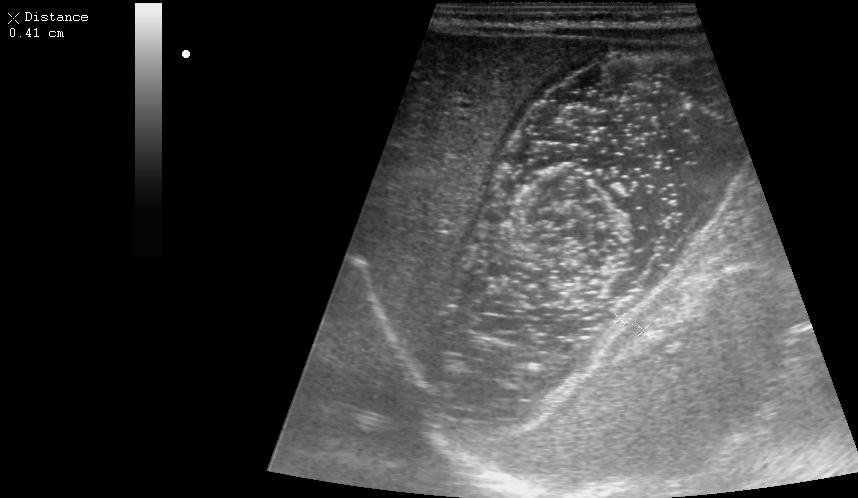

Ребёнок 1 месяц 10 дней от родy, с отсуствием прибавки в весе.

Hypertrophic pyloric stenosis.

Criteria:

1.Pyloric channel > 12 mm in length

2.Muscular layer thickness > 3-4 mm

3.Donuts sign at transverse scanning

Признак "пончика".

А что, похоже.